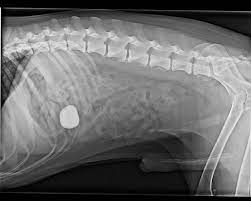

Die meisten einfachen darmverschlüsse können mit großer wahrscheinlichkeit auf einem röntgenbild identifiziert werden. Apr 17, 2009 · katze darmverschluss kotzen, katze bricht stündlich, was heißt laparotomie bei einer katze, erbrechen darmverschluss katzen, darmverschluss,uebergeben,katze, verdacht auf darmverschluss katzen, darmgeschwuer katzen, erbrechen nach darmverschluss bei katzen, darmverschluss katze und erbrechen, katze.darmverschluss erbrechen, katze darmverschluss übergeben, Hierfür öffnet der tierarzt unter narkose den darm (enterotomie) und entfernt den fremdkörper, sodass der katzendarm wieder frei wird. Die darmmuskulatur kontrahiert sich nicht ausreichend um den nahrungsbrei fort zu transportieren. Ohne eine operation versterben diese patienten jedoch häufig. Gerade das sorgfältige abtasten des bauchs kann viele wichtige hinweise liefern. Dabei ist eine einstellung des dünndarms in den dickdarm die häufigste form. Vor allem in fällen mit nicht eindeutiger symptomatik kann auch die verwendung von kontrastmittel notwendig sein. Folgen sind ein gefährlicher rückstau des nahrungsbreis und dadurch. Ein darmverschluss bei einer katze ist eine sehr ernste angelegenheit. Das problem dabei ist, dass ein darmverschluss nicht leicht zu erkennen ist. Darmverschluss bei katzen muss operiert werden. Beginn jeder klinischen diagnostik stellt eine gründliche allgemeinuntersuchung dar.

Natürlich sind einzelnen symptome kein klares indiz für einen darmverschluss, sondern können auch ganz andere ursachen haben. Durch wiederholte röntgenaufnahmen kann dann der transport des futterbreis im darm verfolgt werden. Handelt es sich um einen fortgeschrittenen fall, sind womöglich schon teile des darms abgestorben oder stark beschädigt. Folgen sind ein gefährlicher rückstau des nahrungsbreis und dadurch. Gerade das sorgfältige abtasten des bauchs kann viele wichtige hinweise liefern. Wenn ihr tier auch wasser erbricht sollten sie eine tierärztliche notsprechstunde aufsuchen oder ihren gewohnten tierarzt. Ohne eine operation versterben diese patienten jedoch häufig. In seltenen fällen wird eine diagnostische operation durchgeführt um die ursache mit letzter sicherheit zu klären. Meist kommt es auch bei aufnahme von wasser zu erneutem erbrechen. Die meisten einfachen darmverschlüsse können mit großer wahrscheinlichkeit auf einem röntgenbild identifiziert werden. Ist der darmverschluss bei der katze vonnöten? Gerade bei wiederholtem erbrechen, bei dem auch kein wasser mehr aufgenommen werden kann, kommt es schnell zur austrocknung und infolgedessen zu beeinträchtigungen des kreislaufs. Sie sollte ihrem tier dann vorerst kein futter anbieten.